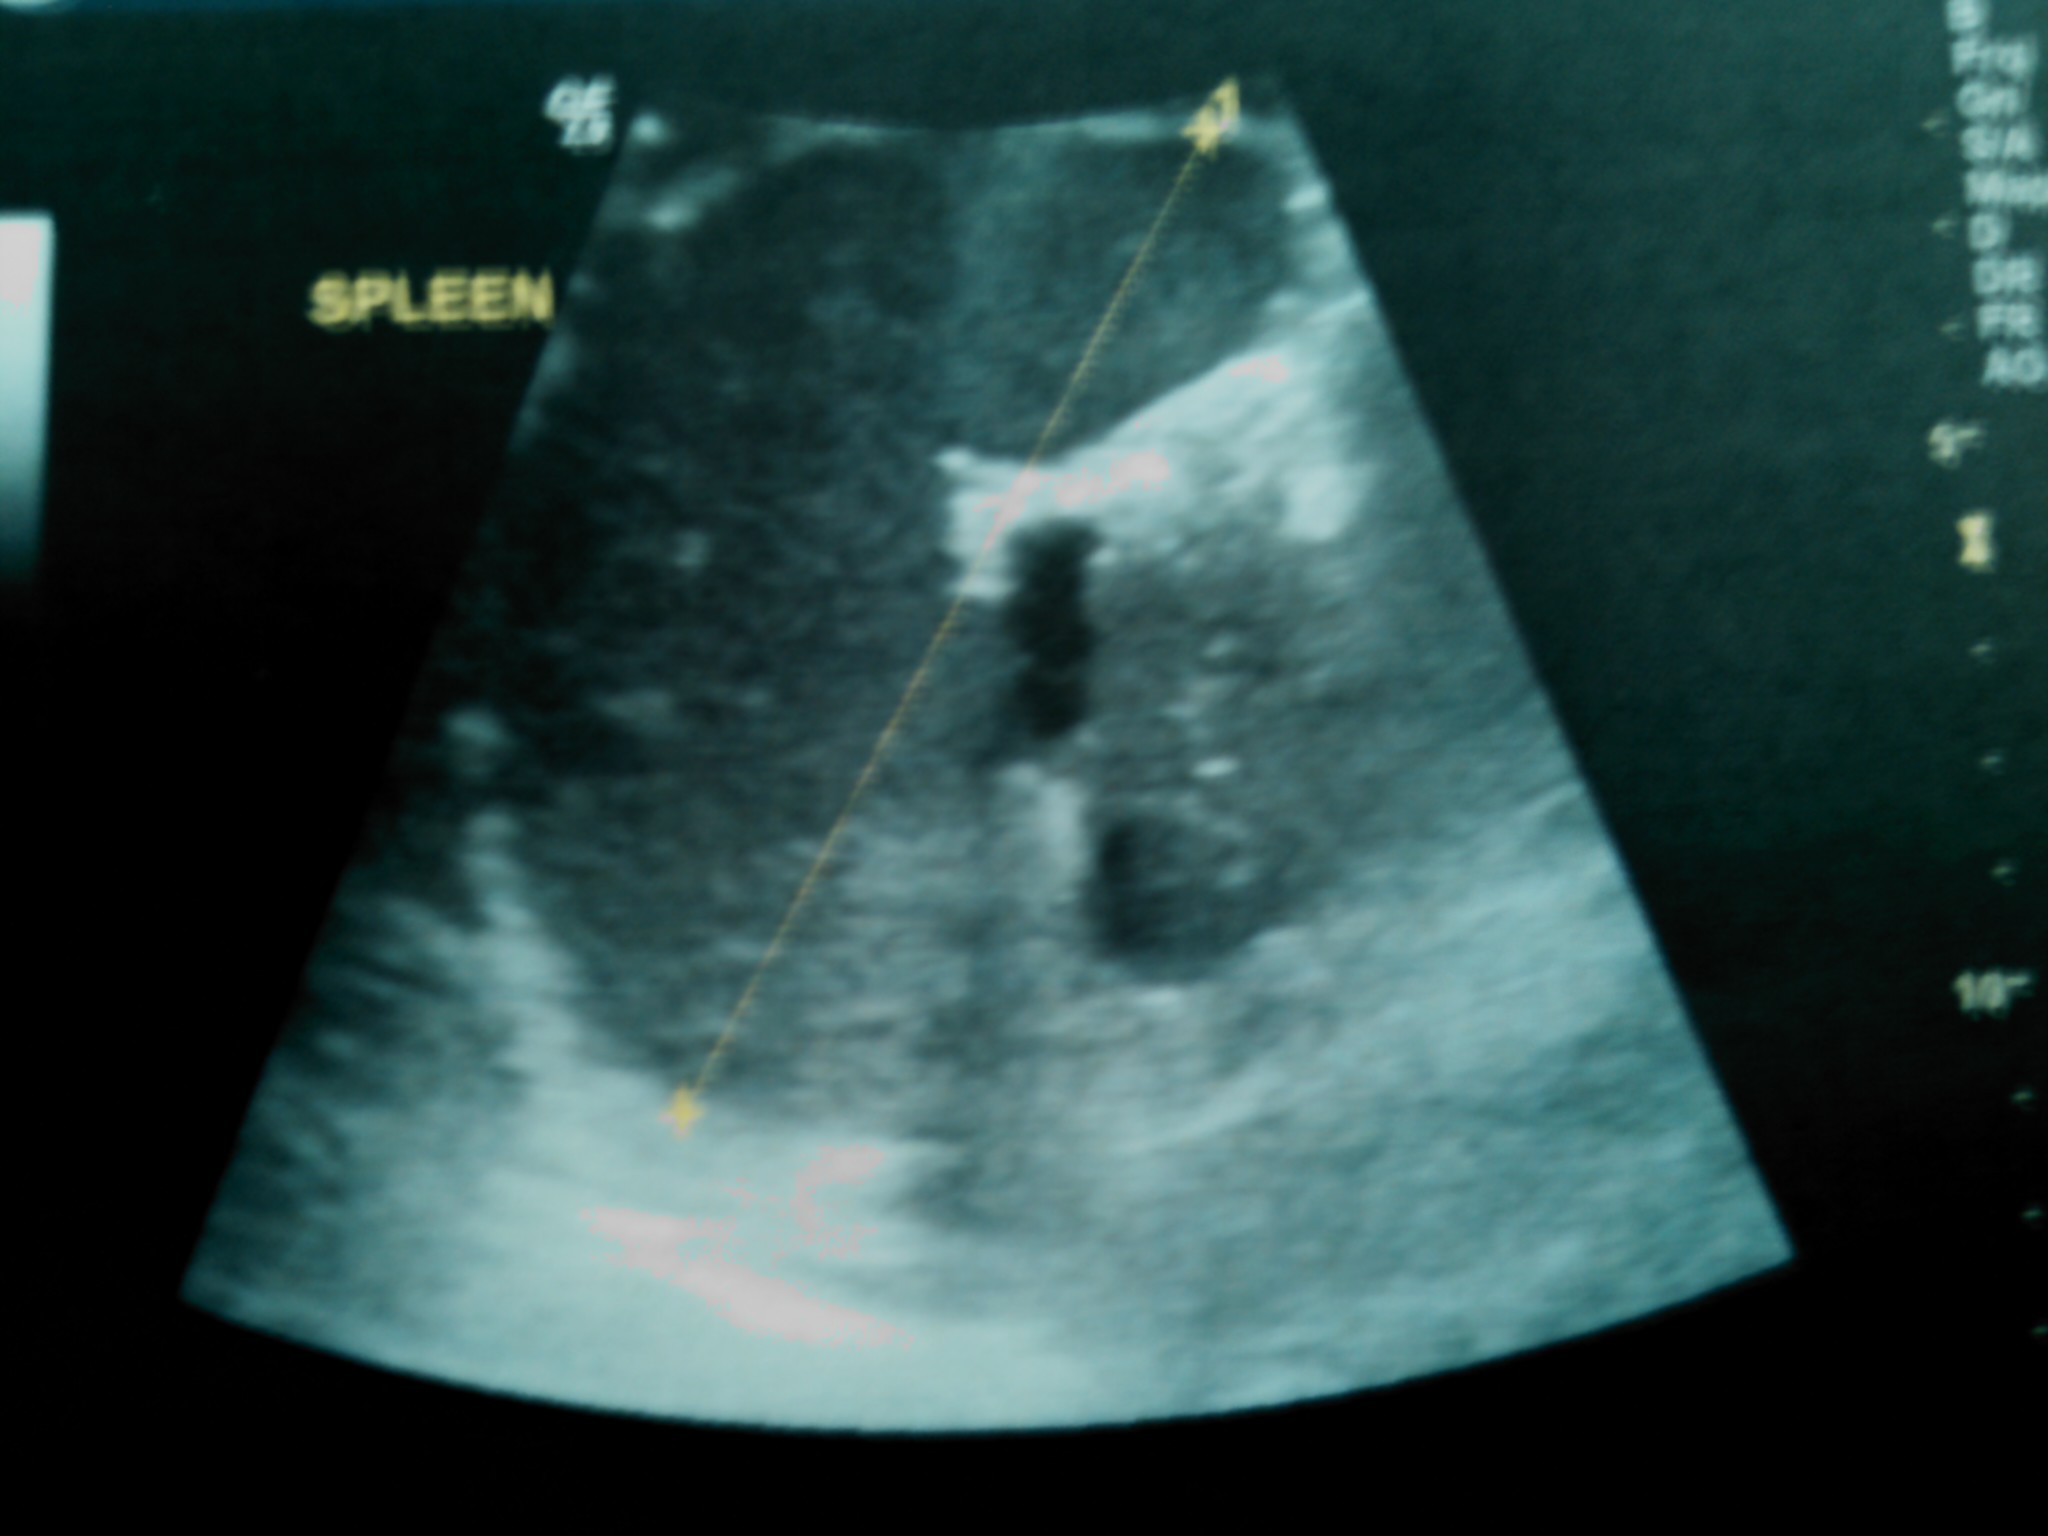

Adalimumab-Associated Isolated Splenic Tuberculosis In A Patient With Psoriasis Following A Negative Screening With Tuberculin Skin Test And QuantiFERON-Gold

We describe a rare form of extrapulmonary tuberculosis and, to our knowledge, the first reported case of isolated splenic tuberculosis in association with adalimumab treatment. In addition, our case demonstrates that the interpretation of a negative tuberculin skin test may prove problematic even in otherwise healthy individuals with no predisposing factors, especially in the face of biologic treatment. A history of BCG vaccination in adulthood may pose additional burdens in the evaluation of such patients facing the risks of anti-TNF agents. As to QuantiFERON, further investigation is warranted in order to be incorporated in the screening for latent tuberculosis infection.Downloads